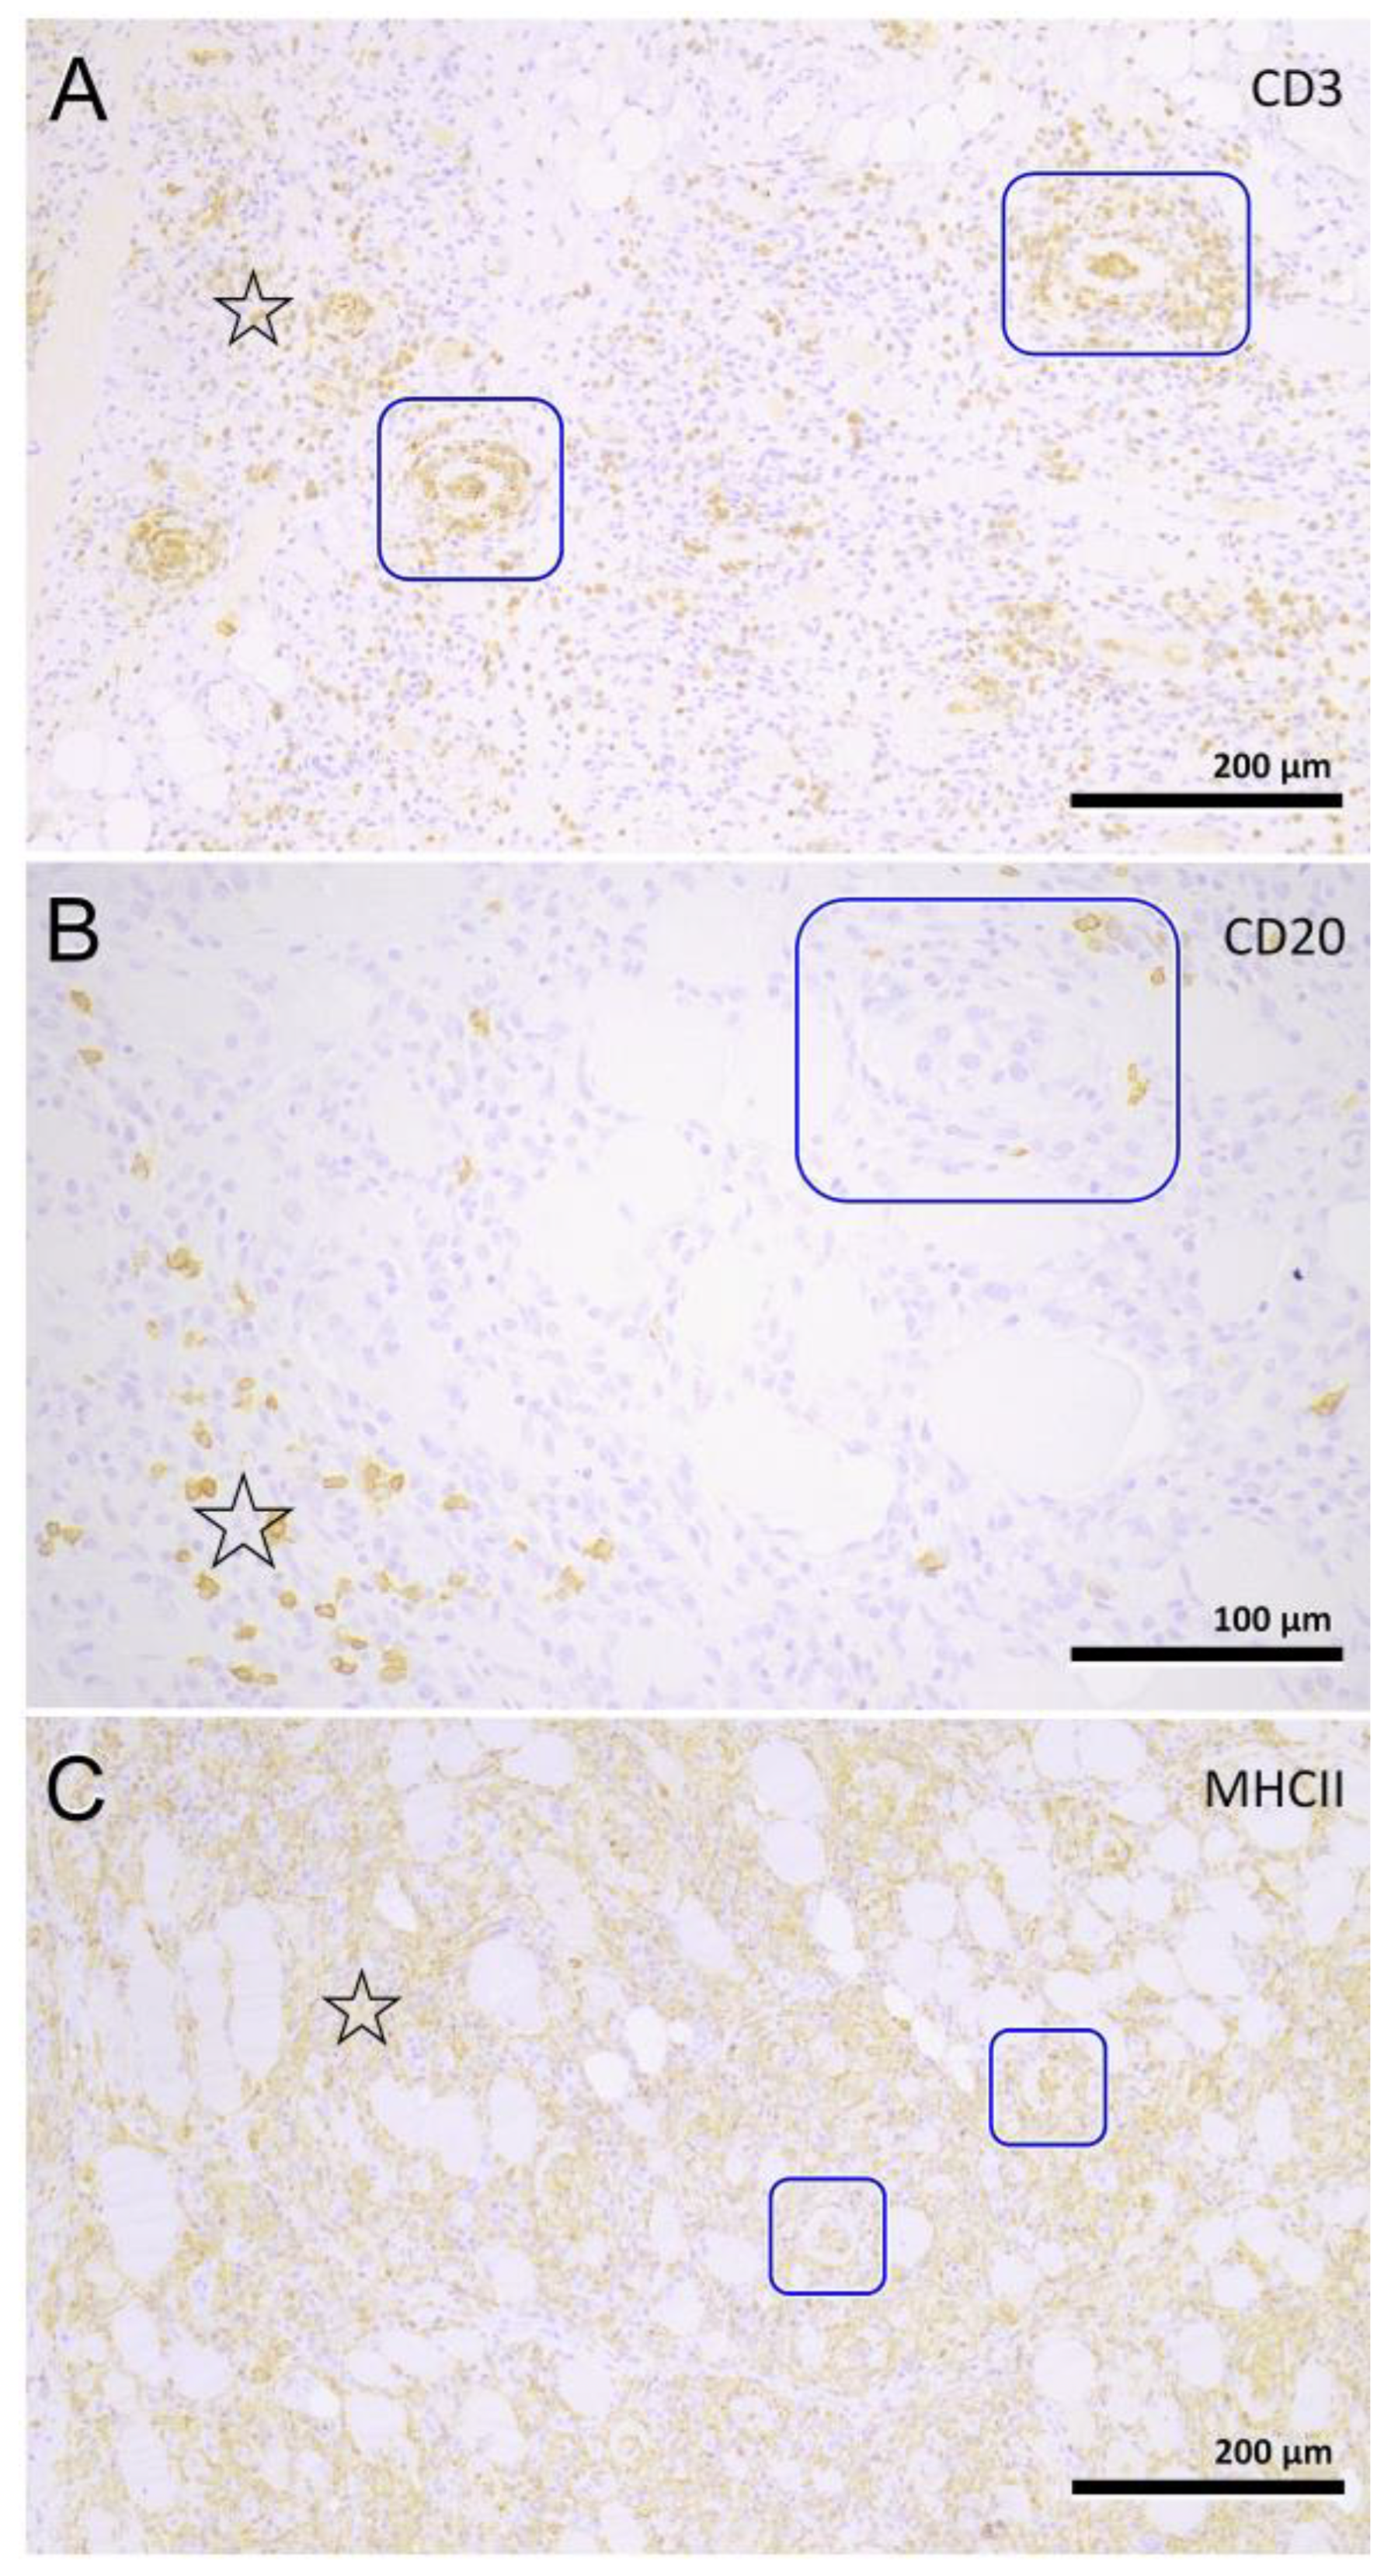

3.4. Histopathology